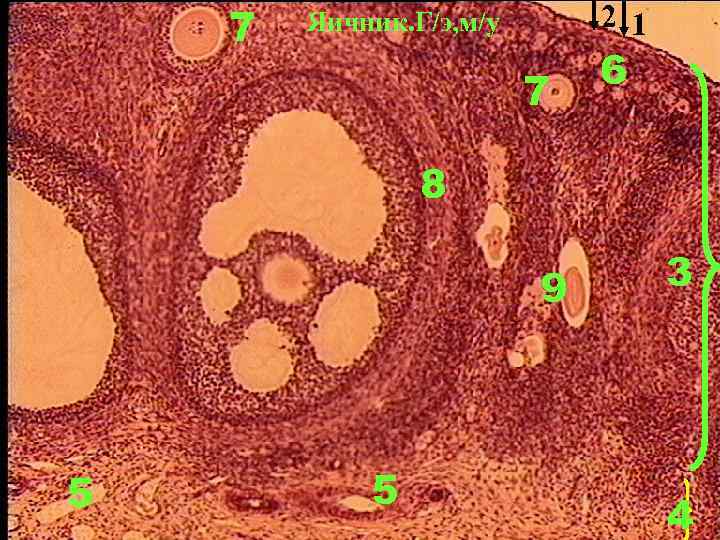

Срез яичника кошки

Срез яичника кошки 105 фотографий